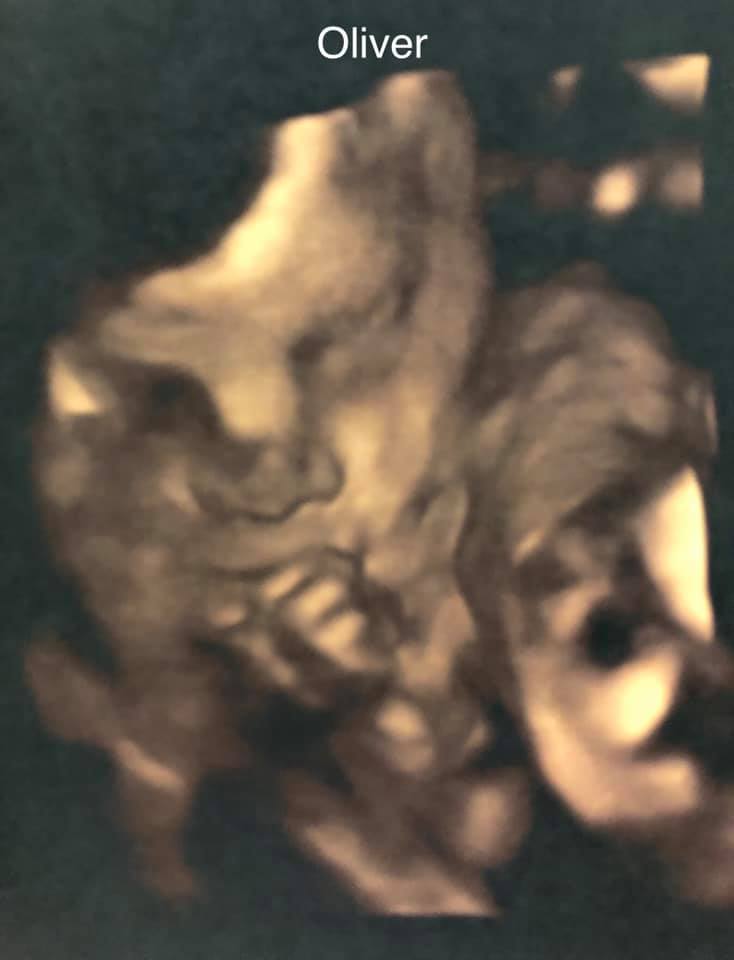

Ultrasound photos at 29 weeks pregnant with twins